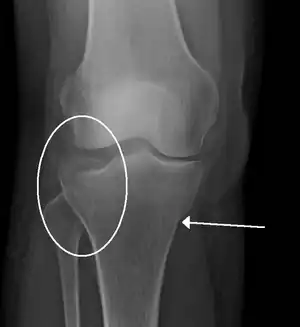

A tibial plateau fracture seen on X-ray

Subtle tibial plateau fracture on an AP X ray of the knee